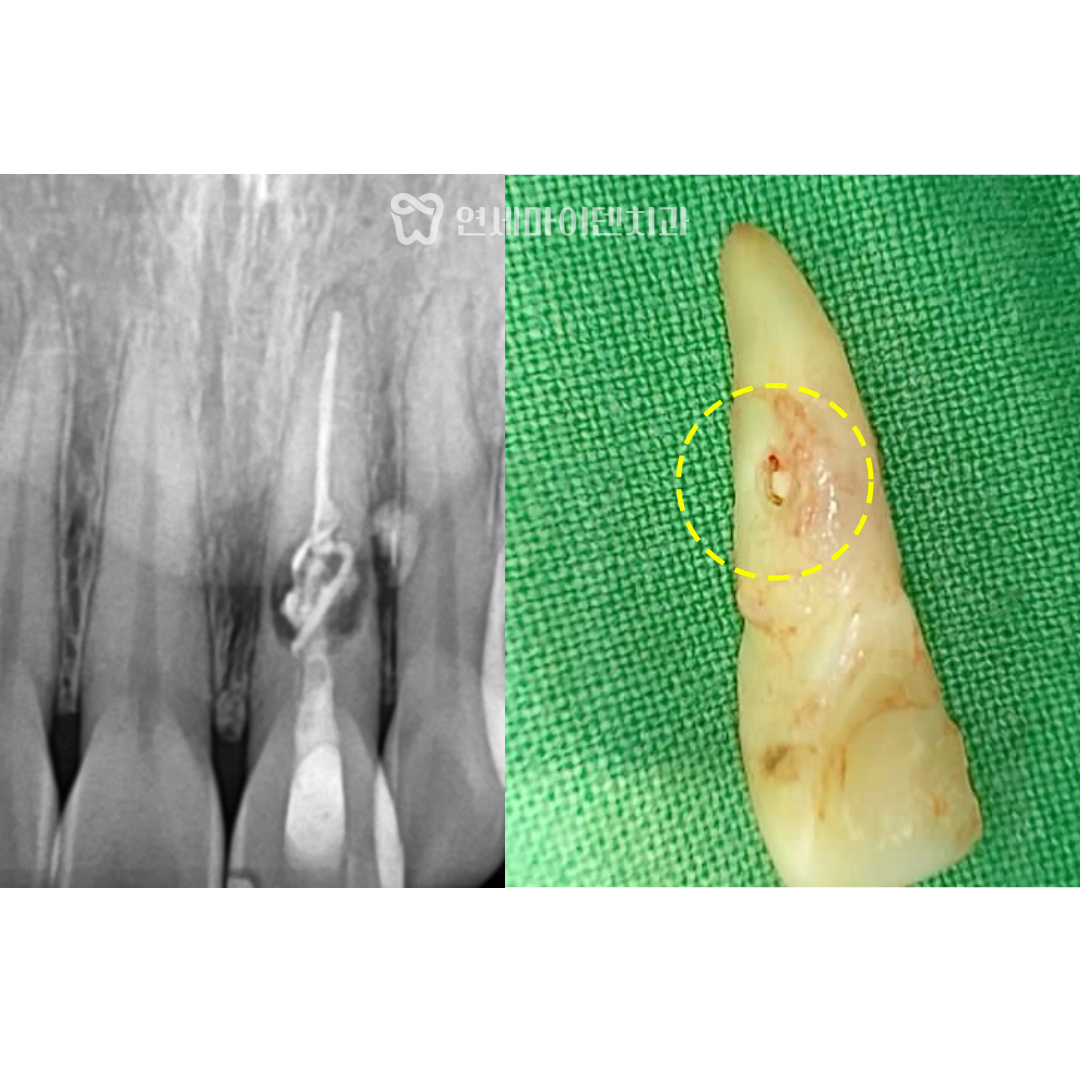

환자분의 치아 방사선 사진을 살펴보면

뿌리쪽 뼈가 까맣게 녹았고, 옆쪽으로 빠져나간 약제도 보입니다.

문제의 앞니를 발치한 뒤 발치된 치아 상태를 살펴보면

뿌리 한가운데 구멍이 뚫려있는 것이 확인됩니다.

뿌리 끝쪽부터 손상이 됐다면 손상된 부분만 절제하는

치근단 절제술을 시도할 수 있지만,

이렇게 가운데 구멍이 뚫린 경우 손상된 부위만 치료하기 어렵기 때문에

발치를 해야하는 상황이 맞았다고 볼 수 있습니다.